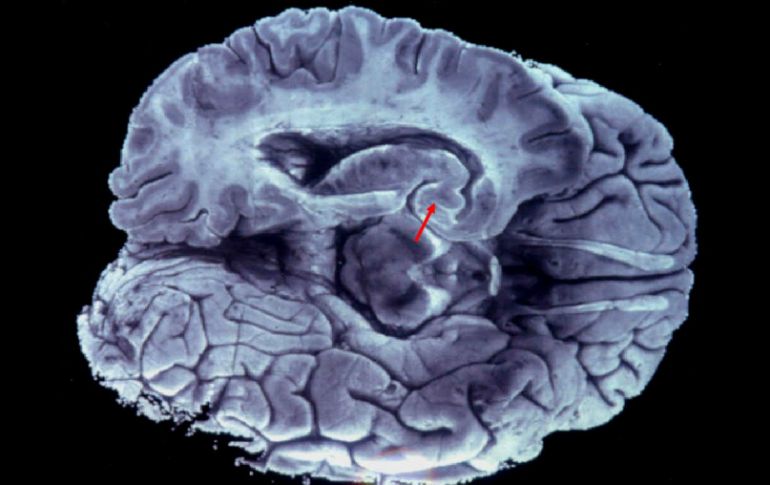

Tecnología | Revelan que el cerebro es capaz de reconectarse correctamente después del nacimiento Es posible recuperar conexiones cerebrales perdidas: estudio Revelan que el cerebro es capaz de reconectarse correctamente después del nacimiento Por: EFE 21 de enero de 2016 - 15:47 hs Es importante la función de la actividad eléctrica temprana en el cerebro. EFE / ARCHIVO MADRID, ESPAÑA (21/ENE/2016).- La actividad del cerebro en los primeros días de vida es esencial para que las conexiones entre los dos hemisferios se establezcan correctamente, según un estudio en el que se prueba, en ratones, que tras el nacimiento existe un período de tiempo en el que sería posible recuperar las conexiones perdidas. Estas son algunas de las principales conclusiones de un trabajo que publica la revista Neuron. que está liderado por científicos del Centro Nacional de Biotecnología (CNB) del CSIC español. Millones de fibras conectan una mitad y otra del cerebro de mamíferos, que juntas forman el cuerpo calloso y transmiten información esencial para que los dos hemisferios cerebrales puedan comunicarse entre sí, señala el CNB en una nota. Si este cableado no se forma bien durante el desarrollo postnatal, los hemisferios funcionarán de manera descoordinada, lo que llevará a la pérdida de las funciones superiores del cerebro y a enfermedades mentales con origen en el desarrollo. En este trabajo, los investigadores explican que la actividad neuronal durante los primeros días tras el nacimiento, orquestada por la expresión de Cux1 -una proteína que influye en la diferenciación neuronal-, "es esencial para que esta autopista de información se forme correctamente". "Hasta ahora no se había comprendido esta importante función de la actividad eléctrica temprana en el cerebro. Nosotros hemos visto que es esencial para un correcto cableado entre hemisferios", detalla Marta Nieto, del CNB y autora del trabajo. Según Nieto, "Cux1 influye en la actividad de la neurona en el cerebro en desarrollo. Gracias a esto controla, en última instancia, la formación de las conexiones". Cuando los científicos inactivaron el gen Cux1 en embriones de ratón, las neuronas dejaron de expresar en sus membranas otra proteína (Kv1) provocando una actividad eléctrica anormal, y como consecuencia, la neurona fue incapaz de formar la conexión a través del cuerpo calloso. Se sabe que en el cerebro adulto cada neurona tiene su actividad característica, un código que le sirve para comunicarse con otras células del circuito. Este trabajo demuestra que ya durante el proceso de formación del circuito, la actividad propia de cada neurona contiene información que determina con quién va a ser capaz de conectarse. Pero, además, prueba que si se recupera la función de estas proteínas tras el nacimiento, el cerebro es capaz de reconectarse correctamente. "Durante un tiempo limitado después del nacimiento podemos restaurar las conexiones perdidas", apunta Carlos García Briz, otro de los autores. Los investigadores fueron capaces de hacerlo en embriones de ratón durante las dos primeras semanas, lo que en humanos podría corresponder a los primeros meses de vida, informaron a Efe fuentes del CNB. Según García, esto sugiere que "podría haber esperanza de recuperación en condiciones patológicas humanas relacionadas con una incorrecta formación del cuerpo calloso o una pérdida de conexiones neuronales de otros tipos". "Nos gustaría continuar esta línea de trabajo e intentar alargar esta ventana de tiempo en la que es posible recuperar la función perdida". Temas Estudios científicos Ciencia médica Cerebro Neurología Lee También Estudio chino revela una mutación que eleva riesgo de alzhéimer ¿Cómo se forman los recuerdos en la mente? La tendencia a hacer ejercicio se trasmite de padres a hijos y esta es la explicación de la ciencia Julieta Fierro será homenajeada en la FIL Recibe las últimas noticias en tu e-mail Todo lo que necesitas saber para comenzar tu día Registrarse implica aceptar los Términos y Condiciones